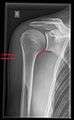

X-ray

These include:

- AP-projection 40° posterior oblique after Grashey

The body has to be rotated about 30 to 45 degrees towards the shoulder to be imaged, and the standing or sitting patient lets the arm hang. This method reveals the joint gap and the vertical alignment towards the socket.[19]

CR. shoulay film.